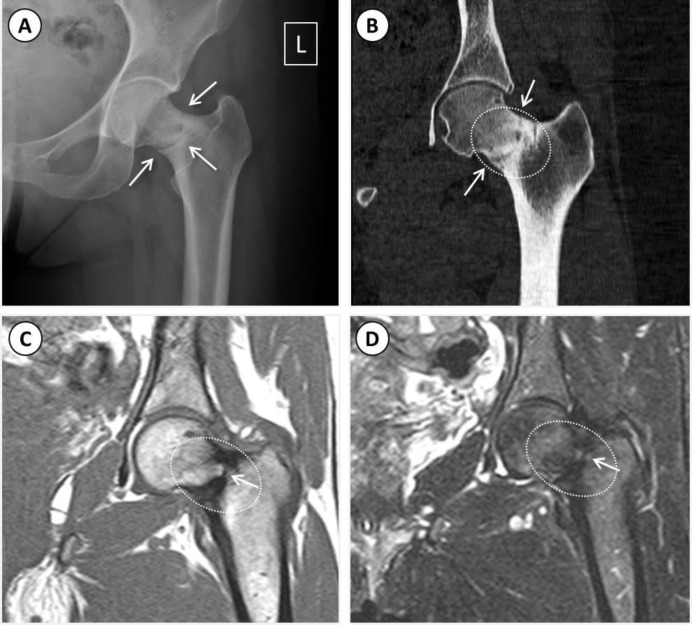

股骨颈疲劳骨折。

Fatigue Fracture of the Femoral Neck.